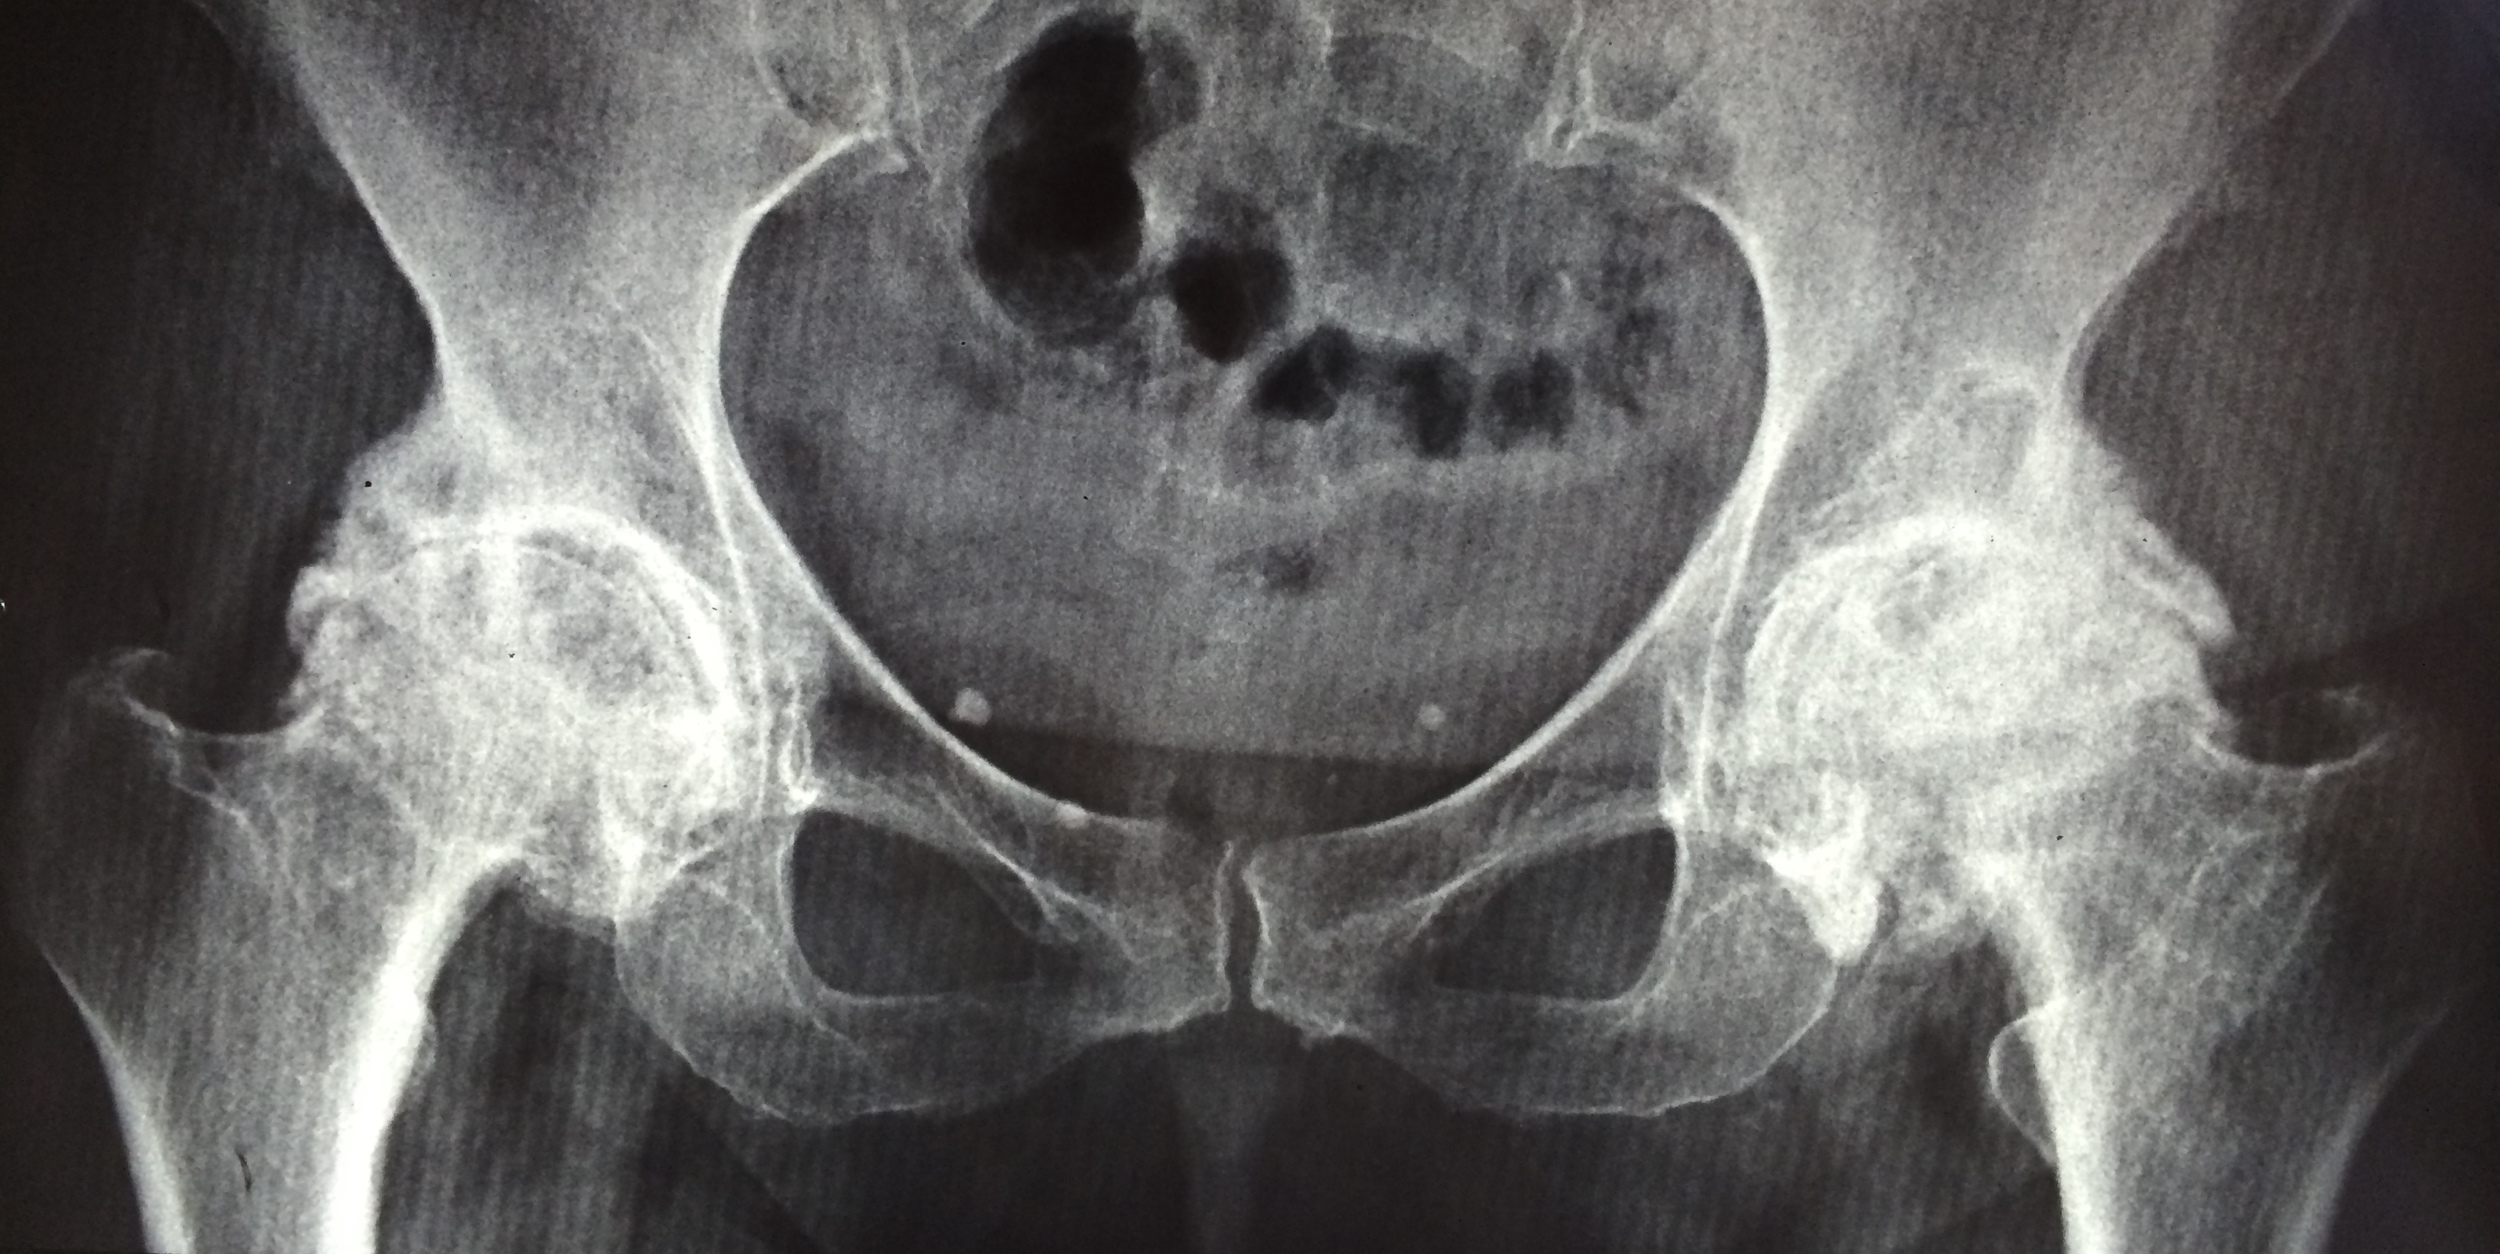

2º Consulta cadeira de rodas - Artrose severa em ambos quadris. Muita dor e impossibilidade de se locomover sem auxilio.

[caption id align="alignnone" width="2500"]

Artrose severa de quadril bilateral [/caption] [caption id align="alignnone" width="1028"]